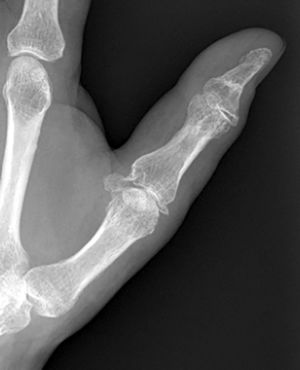

Caso clínicoPaciente de 56 años, en estado etílico, es trasladado a Urgencias con una herida contusa en la nariz tras una caída al suelo. Después de suturarla, se decide su observación durante unas horas. En el momento del alta, el paciente se queja de su mano izquierda, la cual se encuentra, a nivel del pulgar, inflamada y equimótica, con una erosión de 0,5cm2 situada en el lado radial de la articulación MCF. El estudio radiográfico muestra fractura-avulsión de ambos ligamentos colaterales de la articulación MCF del pulgar (fig. 1). Con anestesia troncular axilar, se explora mediante control fluoroscópico la estabilidad de la articulación y se comprueba que tanto en extensión como en flexión de 30° no existen bostezos apreciables que denoten la total rotura de los ligamentos colaterales, motivo por el cual se decide el tratamiento conservador mediante un yeso de escafoides durante 4 semanas, tras las cuales se permite la movilidad libre del pulgar. Un año más tarde, el paciente se halla libre de dolor y sin inestabilidad. Sin embargo, el estudio radiográfico objetiva la existencia de una falta de unión en ambas fracturas (fig. 2).